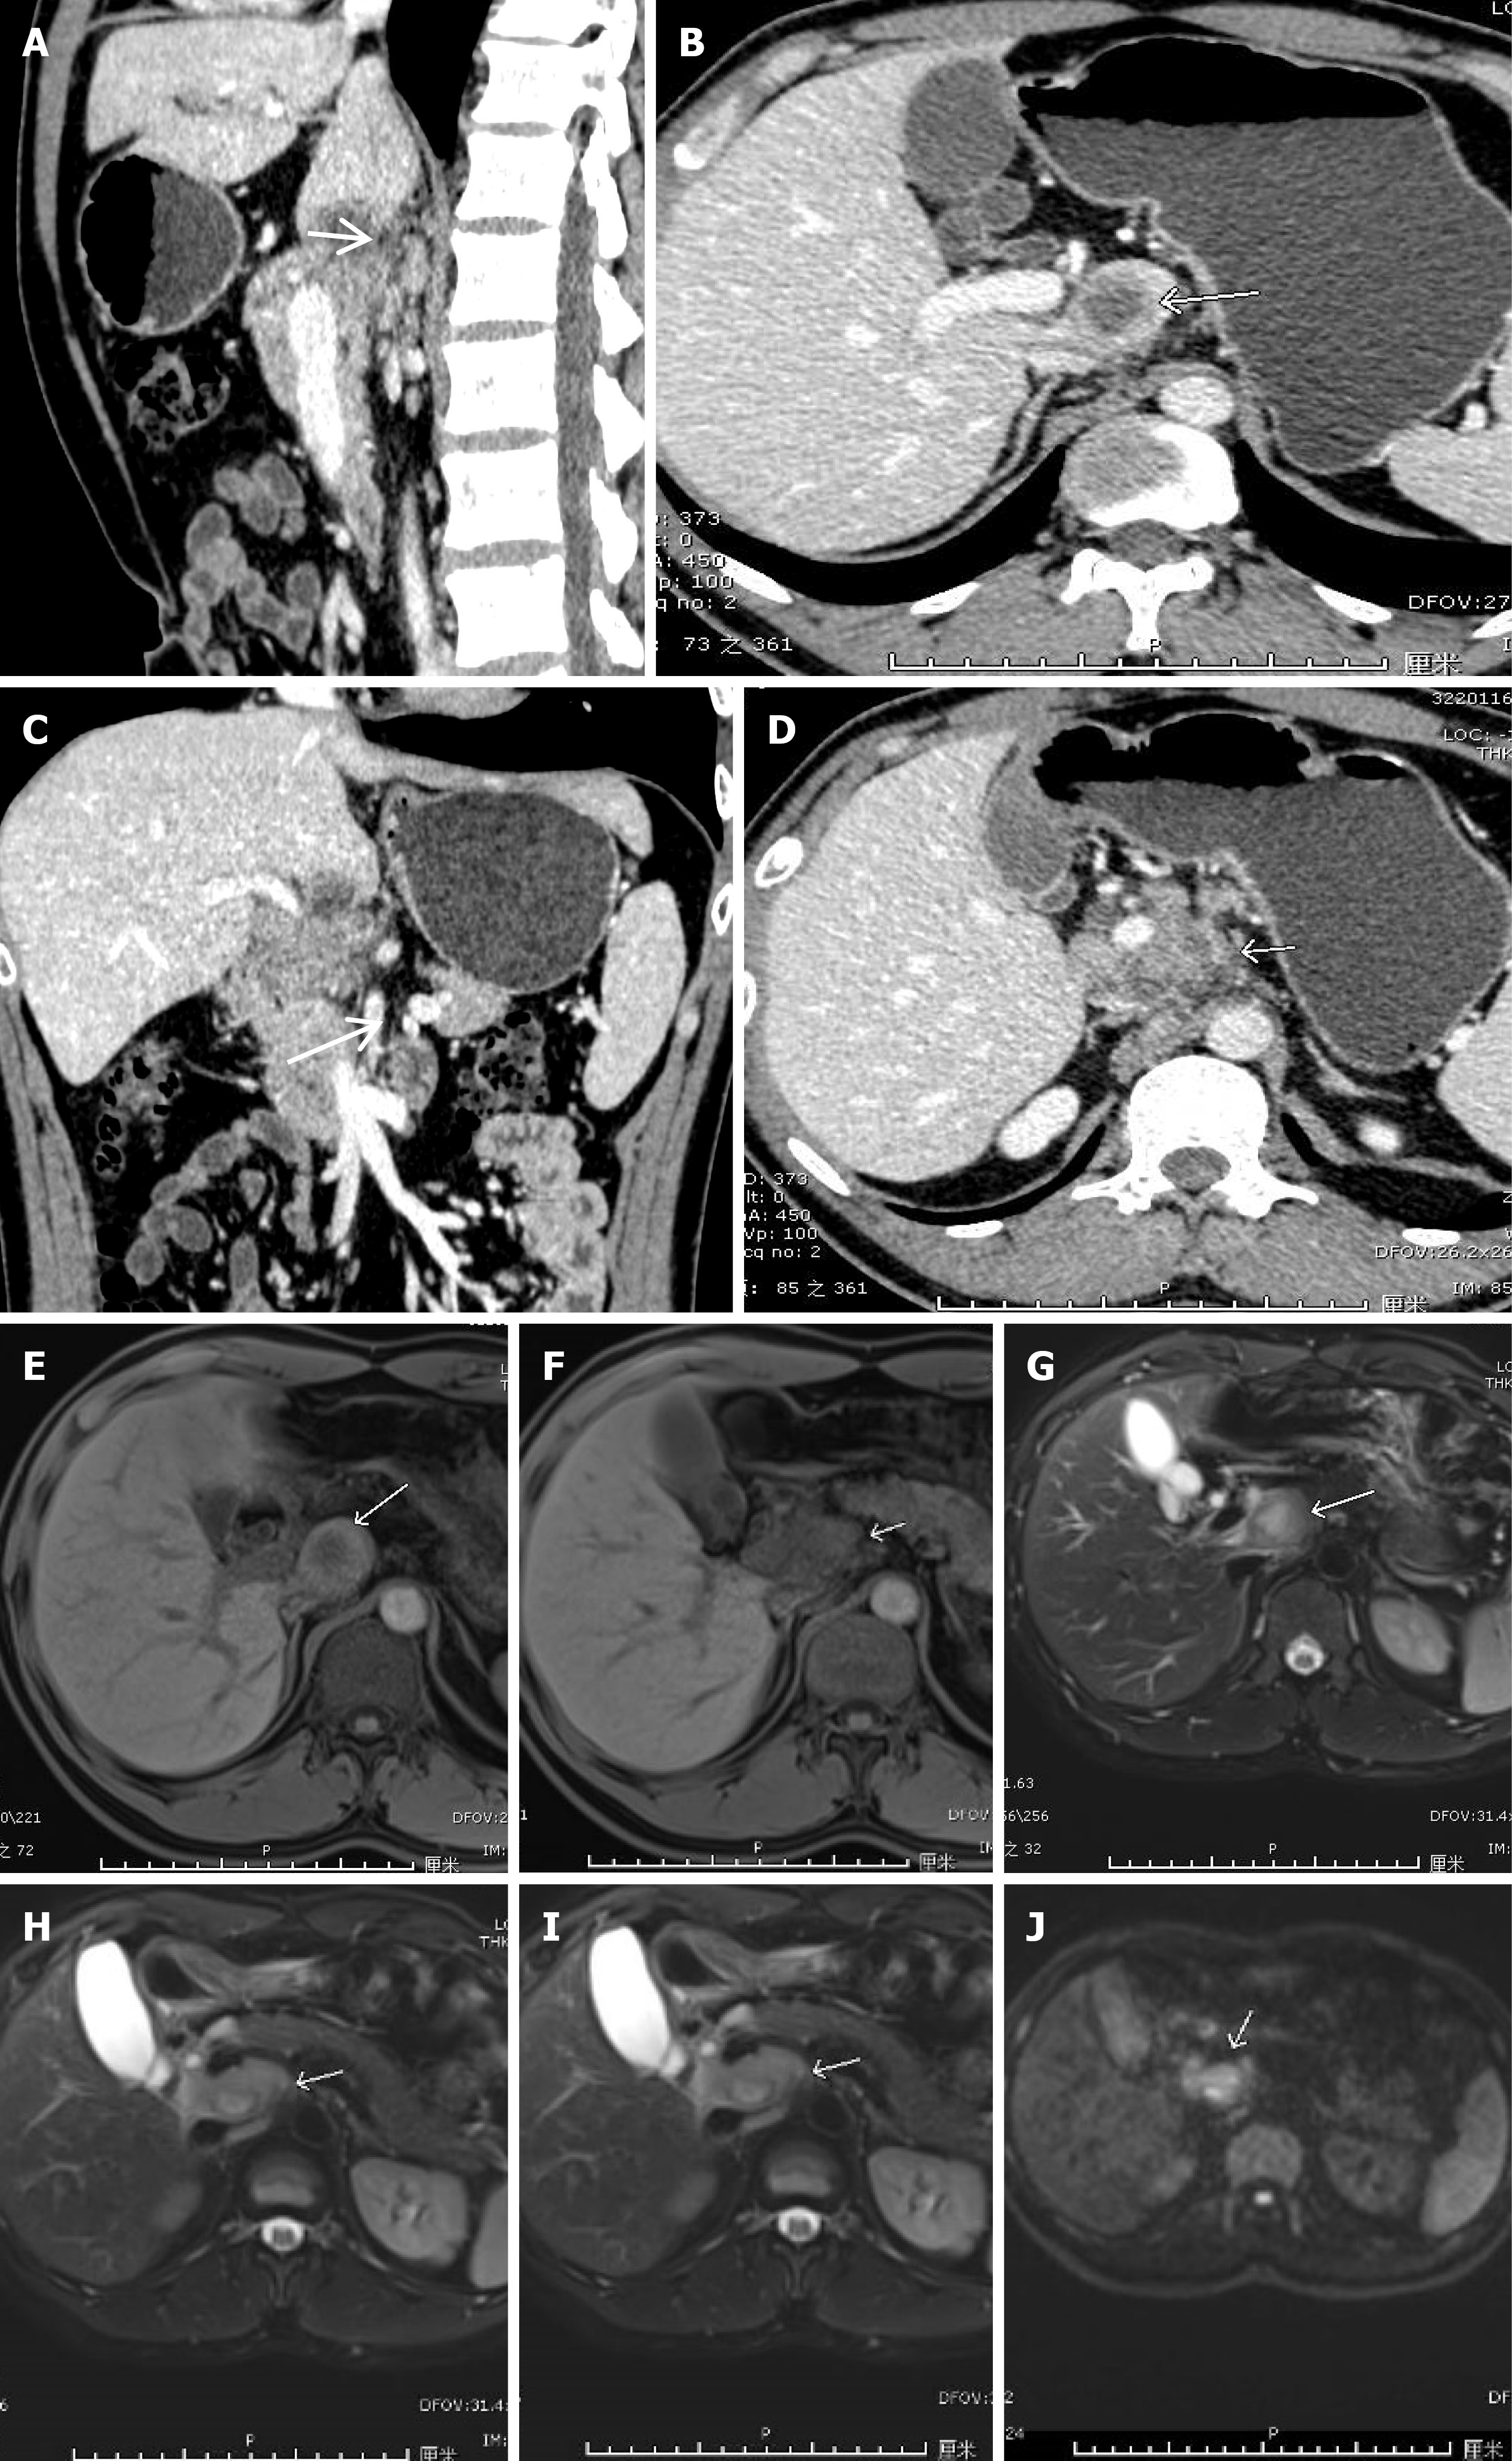

Figure 1 Computed tomography and magnetic resonance imaging images of the liver.

A: Sagittal plane showing lesions in the caudal lobe region (arrow); B: Axial position of lesions in the caudal lobe region (arrow); C: Coronal view showing lesions in the caudal lobe region and enlarged lymph nodes below the caudal lobe (arrow); D: Multiple enlarged lymph nodes in the portal space; E: Lesion in caudal lobe region (T1 sequence) (arrow); F: Multiple enlarged lymph nodes in the portal space on T1 sequence (slightly prolonged T2 signal nodules, partially fused) (arrow); G: Caudal lobe region lesion (T2 sequence); H: Multiple enlarged lymph nodes in the portal space on T2 sequence (slightly prolonged T2 signal nodules, partially fused) (arrow); I: Lesion in the caudal lobe region on the enhanced sequence, appearing as a circular enhancement (coronal plane) (arrow); J: Enlarged lymph nodes in the portal space with high signal intensity on diffusion-weighted imaging (arrow).